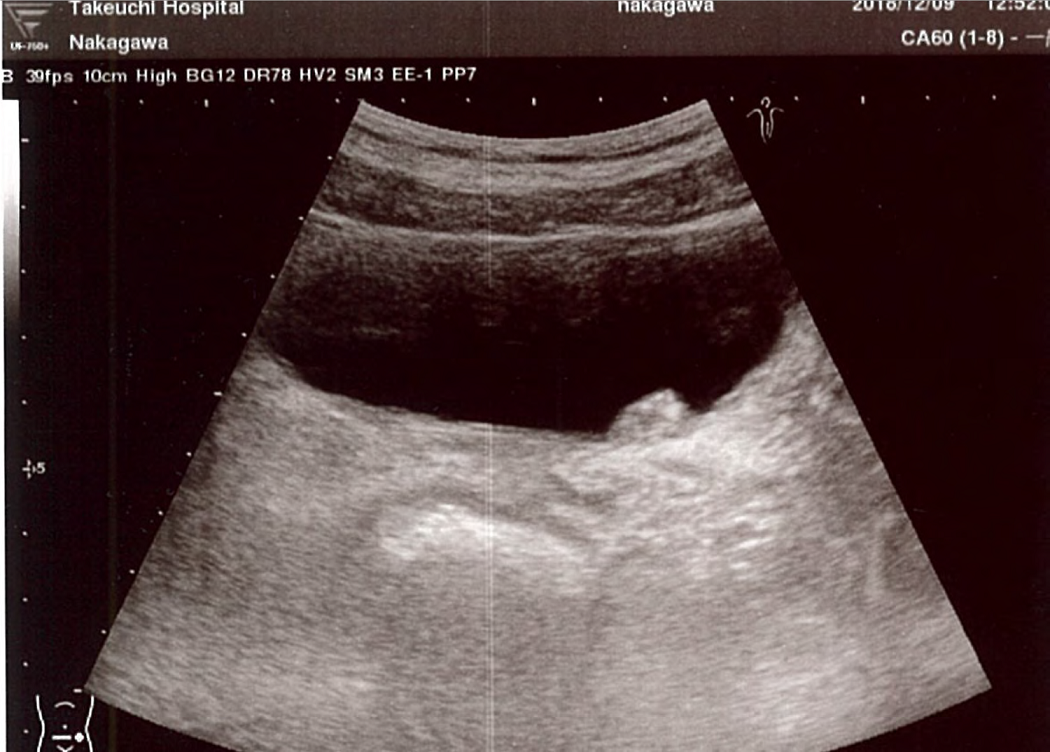

超音波エコーの画像。右上の突き出ている部分ががん細胞=中川先生提供

がんは自分で見つけました。昨年12月9日、先輩の病院で当直のお手伝いをしていたとき、空いている時間に超音波エコーで自分の肝臓を診たのです。

というのも、2年ほど前から肝臓に、肝硬変などの原因になりかねない脂肪肝があったのです。この日はふと気になって、膀胱も映してみました。すると、左の尿管と膀胱のつなぎ目である尿管口の近くに、白い影が見えました。

実は2017年6月に、超音波エコーで膀胱を見た際に、内壁に小さな影を見つけていました。しかし、忙しくて放っておいたのでした。今回の白い影は、それが大きくなったものです。膀胱を映してみたのは、心のどこかで影のことが気になっていたからかもしれません。

見つけた瞬間、「がんに違いない」と思いました。念のため、東大病院の泌尿器科の後輩にメールで画像を送ったところ、「膀胱腫瘍を否定できない所見だと思います」という返信が届きました。良性の可能性もあるが、「頻度はごくわずか」と書いてあります。わずかの可能性に期待しましたが、精密検査の結果、大きさ1.5センチのがんと判明しました。幸い、がんは筋肉の層までは浸潤しておらず、早期でした。血尿もなく、自覚症状はありませんでした。